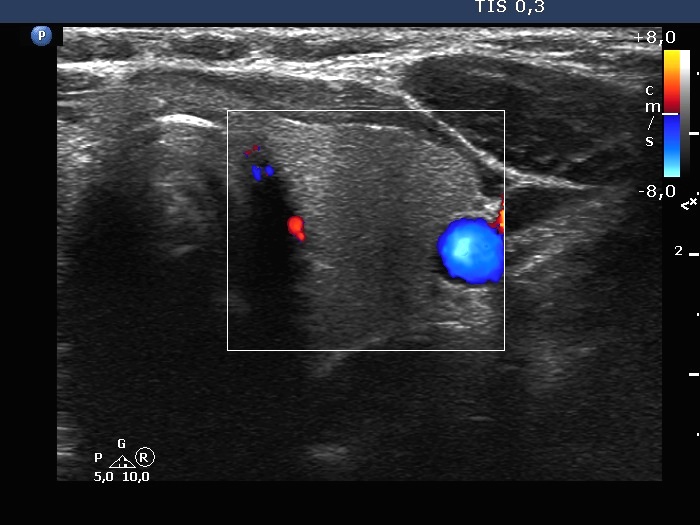

The composition of the nodule - case 2103 (ultrasonographic picture 6)

Right lobe, longitudinal scan

Left lobe, transverse scan, color Doppler mode. The vascularization is decreased.